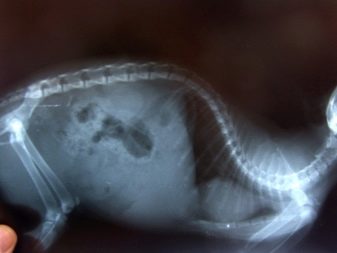

El gat escocès és de mida mitjana. Una mascota adulta pesa de 3,5 a 6 quilograms. Els gatets recent nascuts tenen algun defecte en l'estructura de la columna vertebral, la cua i les extremitats. Quan neixen tots els nadons, les orelles tenen l’aspecte habitual. Quan els gatets compleixen 3 setmanes, es comença a formar un plec a les seves aurícules.

Genèticament, la salut escocesa no es considera ideal. En animals es pot produir deformació òssia, enduriment de la cua i també hi ha problemes de mobilitat. La causa d’aquests problemes és la creu del plec amb el plec. Els representants de la raça escocesa de gats poden patir patologia cardíaca o poliquística renal.